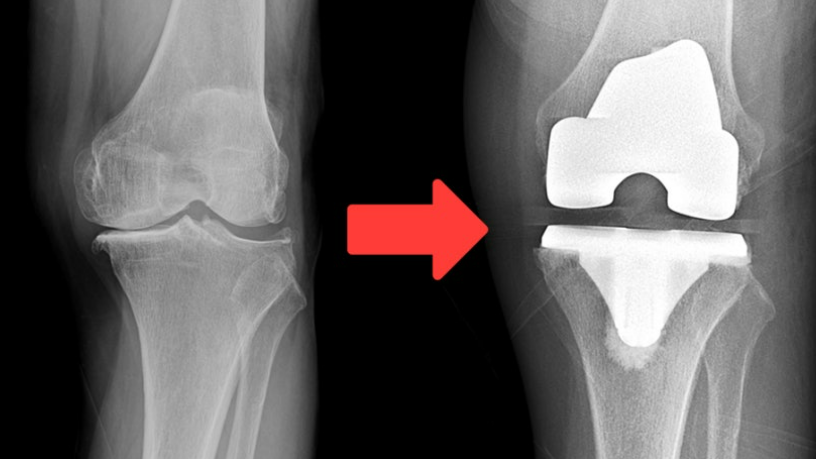

무릎 인공관절 수술은 퇴행성 관절염으로 인해 심각하게 손상된 무릎 관절을 인공 재료로 대체하는 고도의 의료 시술입니다.

이 수술은 주로 보존적 치료로 더 이상 효과를 보지 못하는 노년층 환자들에게 시행되며, 극심한 통증 완화와 일상 생활 기능의 회복을 주요 목적으로 합니다.

수술 과정에서는 손상된 연골과 뼈를 제거하고, 특수 제작된 금속이나 플라스틱 재질의 인공 관절로 대체하여 무릎의 정상적인 기능을 복원합니다.